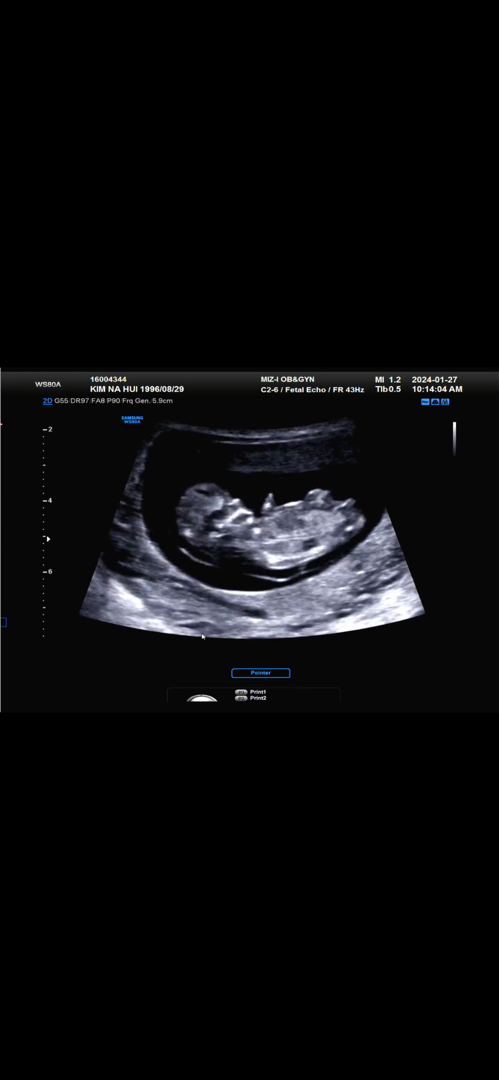

11주2일

각도법 너무 궁금해서 올려보아요 한달뒤 2차기형아검사인데 어떻게 기다리죠…맨날 보고싶네요😭😭